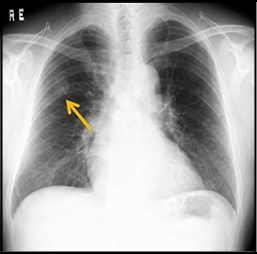

ただ、気になるのは胸のレントゲン写真。

過去4年間の写真を比べてみると

まったく同じ場所に同じ位の白い影。

(画像お借りしました)

取り立てて、診てくれた先生が重要視している様子でもなかったので

オイラ自身も、あまり気にしない事にした。